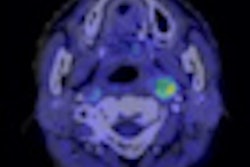

In this scientific paper presentation, researchers from Washington University School of Medicine will present their work on a novel synthesized tracer that so far has shown promising tumor imaging properties in the potential to complement MRI for evaluating patients with primary and metastatic brain tumors.The tracer, knows as α-[F-18]fluoromethyl phenylalanine (FMePhe), has been tested in microPET studies in a mouse model of high-grade gliomas.

McConathy and Chaofeng Huang, PhD, a postdoctoral research associate in the division of radiological sciences, noted that the microPET data demonstrated good tumor visualization within 10 minutes of injection, as well as persistent activity in the tumor.

In addition, tumor-to-brain signal ratios were 3.9 (± 0.3)-to-1 at 50 to 60 minutes after injection, which is superior to FDG, which achieved tumor-to-brain ratios of approximately 1.3-to-1 at 50 to 60 minutes after injection in this model.